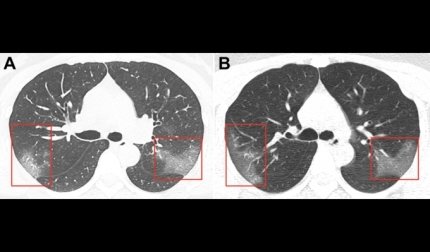

При цьому демонструються два знімка легенів пацієнтки. На першому показані множинні помутніння, що створюють ефект матового скла. Другий знімок був зроблений три дні потому. Він показує, що хвороба прогресує, а область "матового скла" розширюється. Який стан пацієнтки на даний момент, в публікації не вказано.